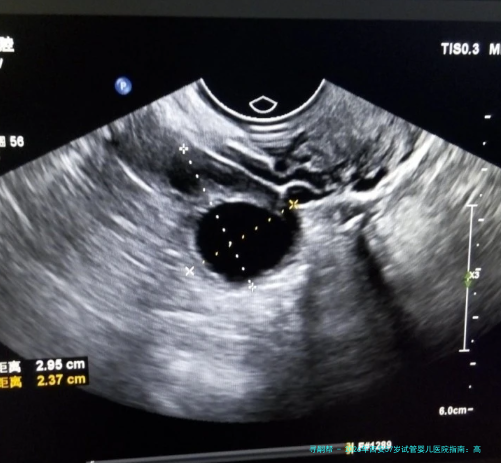

阴道B超监测排卵1508010090-120